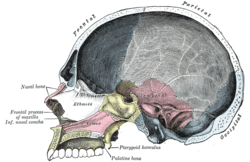

Medial wall of left orbit. Sagittal section of skull.

Sagittal section of skull. Roof, floor, and lateral wall of left nasal cavity.